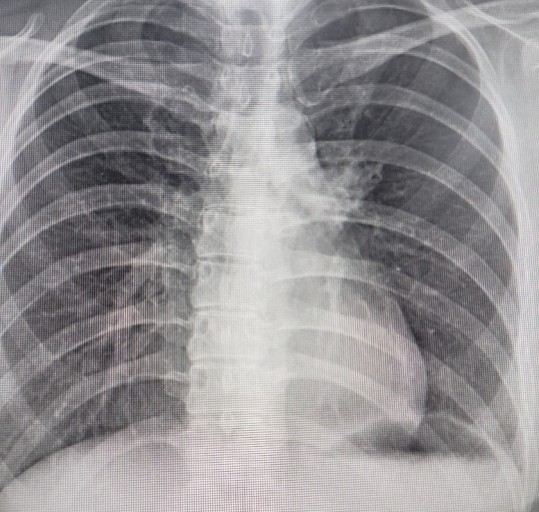

- 정기적인 건강 검진: 특히 흡연자나 가족력이 있는 경우, 저선량 흉부 CT와 같은 정밀 검진을 통해 조기에 발견해야 합니다.